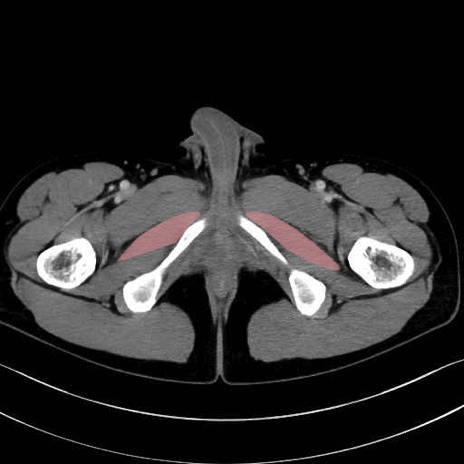

大内転筋(Adductor magnus)、小内転筋(Adductor minimus) のCT画像の解剖

6. 大腿内側(内転筋群)

大内転筋・小内転筋 (Adductor magnus / Adductor minimus)